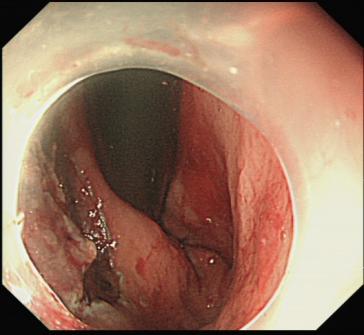

在省人民医院专科联盟指导下ESD手术顺利完成,为什么“完整剥离”如此重要? 因为只有这样,才能将病灶连根拔起,并获取完整的病理标本,为后续的诊断和治疗提供最可靠的依据。也避免了外科开腹手术。

黄女士成功接受了ESD手术。术后病理分析证实了术前的判断:绒毛状管状腺瘤,局灶高级别上皮内瘤变。

正是因为发现得极其及时,黄女士的病情被扼杀在摇篮里。通过ESD这一微创手术,她不仅完整切除了癌变组织,更幸运地保住了肛门和直肠的完整功能,避免了外科开腹手术带来的巨大创伤、更长的恢复期以及可能需要的肠道改道(造口)。术后几天,黄女士便顺利出院,回归正常生活。